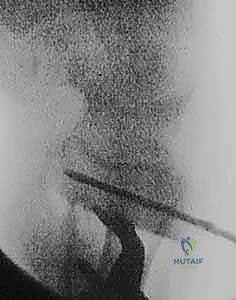

- الأشعة المقطعية (CT Scan) مع إعادة البناء ثلاثي الأبعاد (3D Reconstruction): هذه الخطوة حاسمة. تتيح للدكتور هطيف رؤية العظم من جميع الزوايا، وتحديد مكان القص بدقة متناهية.